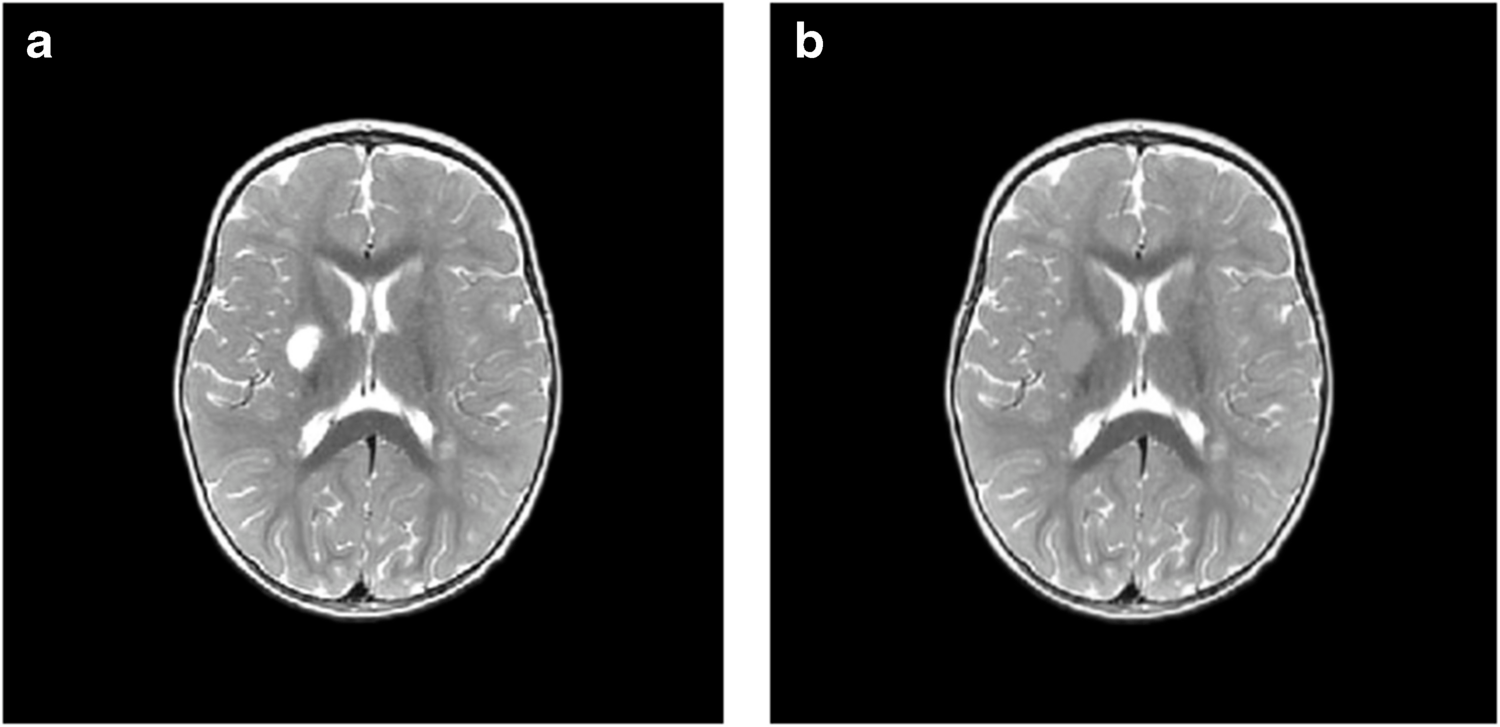

Исследователи проанализировали данные МРТ 35 детей, которые перенесли ишемический инсульт в возрасте до двух лет и лечились в больницах Екатеринбурга, Перми, Челябинска и Тюмени в период с 2015 по 2019 год. Возраст детей на момент инсульта варьировался от четырех дней до одного года 11 месяцев.

Для оценки последствий инсульта исследователи применили современный метод анализа снимков — воксель-базированную морфометрию. Упрощенно эту технологию можно представить так: на каждом МРТ-снимке слой за слоем вручную обводят контуры повреждений области мозга, а специальная компьютерная программа затем вычисляет точный объем этой зоны в кубических миллиметрах. Такая технология позволяет получить наиболее объективные данные по сравнению с традиционным МРТ-отчетом, направленным на определение качественных характеристик (точных границ инсульта, его локализации). Воксель-базированная морфометрия позволяет получить количественные данные: абсолютный и относительный объем поражения от общего объема мозга. Результат применения такого метода — точные числовые значения для последующего статистического анализа и сравнения.

Оказалось, что инсульты у младенцев и детей, достигших месячного возраста, различаются и по масштабам, и по характеру повреждений. Так, у малышей с перинатальным инсультом объем повреждения мозга оказался намного серьезнее, чем у старших: 7,9% против 1,6% от объема мозга. Также у новорожденных чаще встречались нарушения, затрагивающие кору мозга, смешанные и двусторонние инсульты, а у группы детей от 28 дней до двух лет преобладали локальные подкорковые очаги и повреждения только левого полушария.